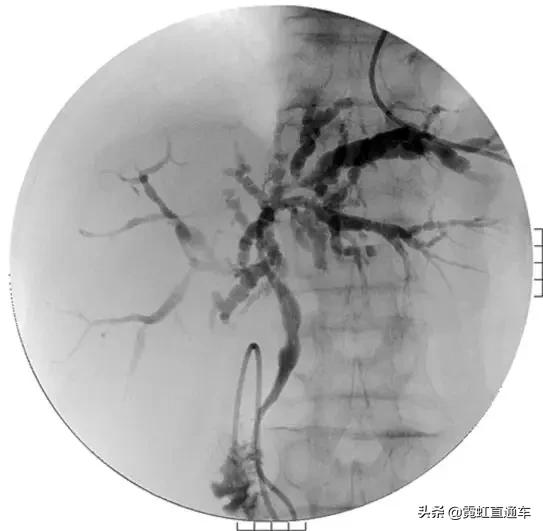

A.胆道影像学检查

1)特异性胆管征象

2)非特异性胆管征象

ERCP:胆管狭窄与扩张交互,呈串珠状改变

多发短小狭窄,胆管环状受累

PTCD:胆管呈边缘不整羽毛状

ERC:胆管壁呈憩室样突出